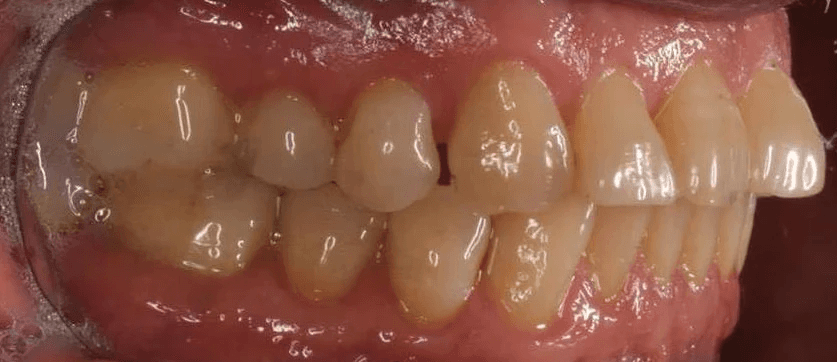

Diagnosis: A mix of crowding and mild spacing, moderate curve of Spee, black triangles, significant overjet, reverse smile display

Adjuncts: Bite ramps, attachments, IPR

Initial treatment

INTRAORAL